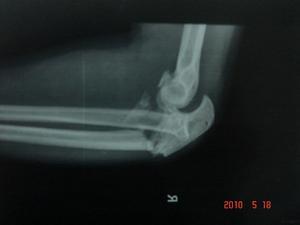

Ⅳ型:為橈骨頭骨折伴有肘關節脫位。

4.Ⅳ型

儘量保留橈骨頭,如果無法復位和內固定,則行橈骨頭置換。此外還需修復肘關節側副韌帶,並以石膏或外固定架固定肘關節。